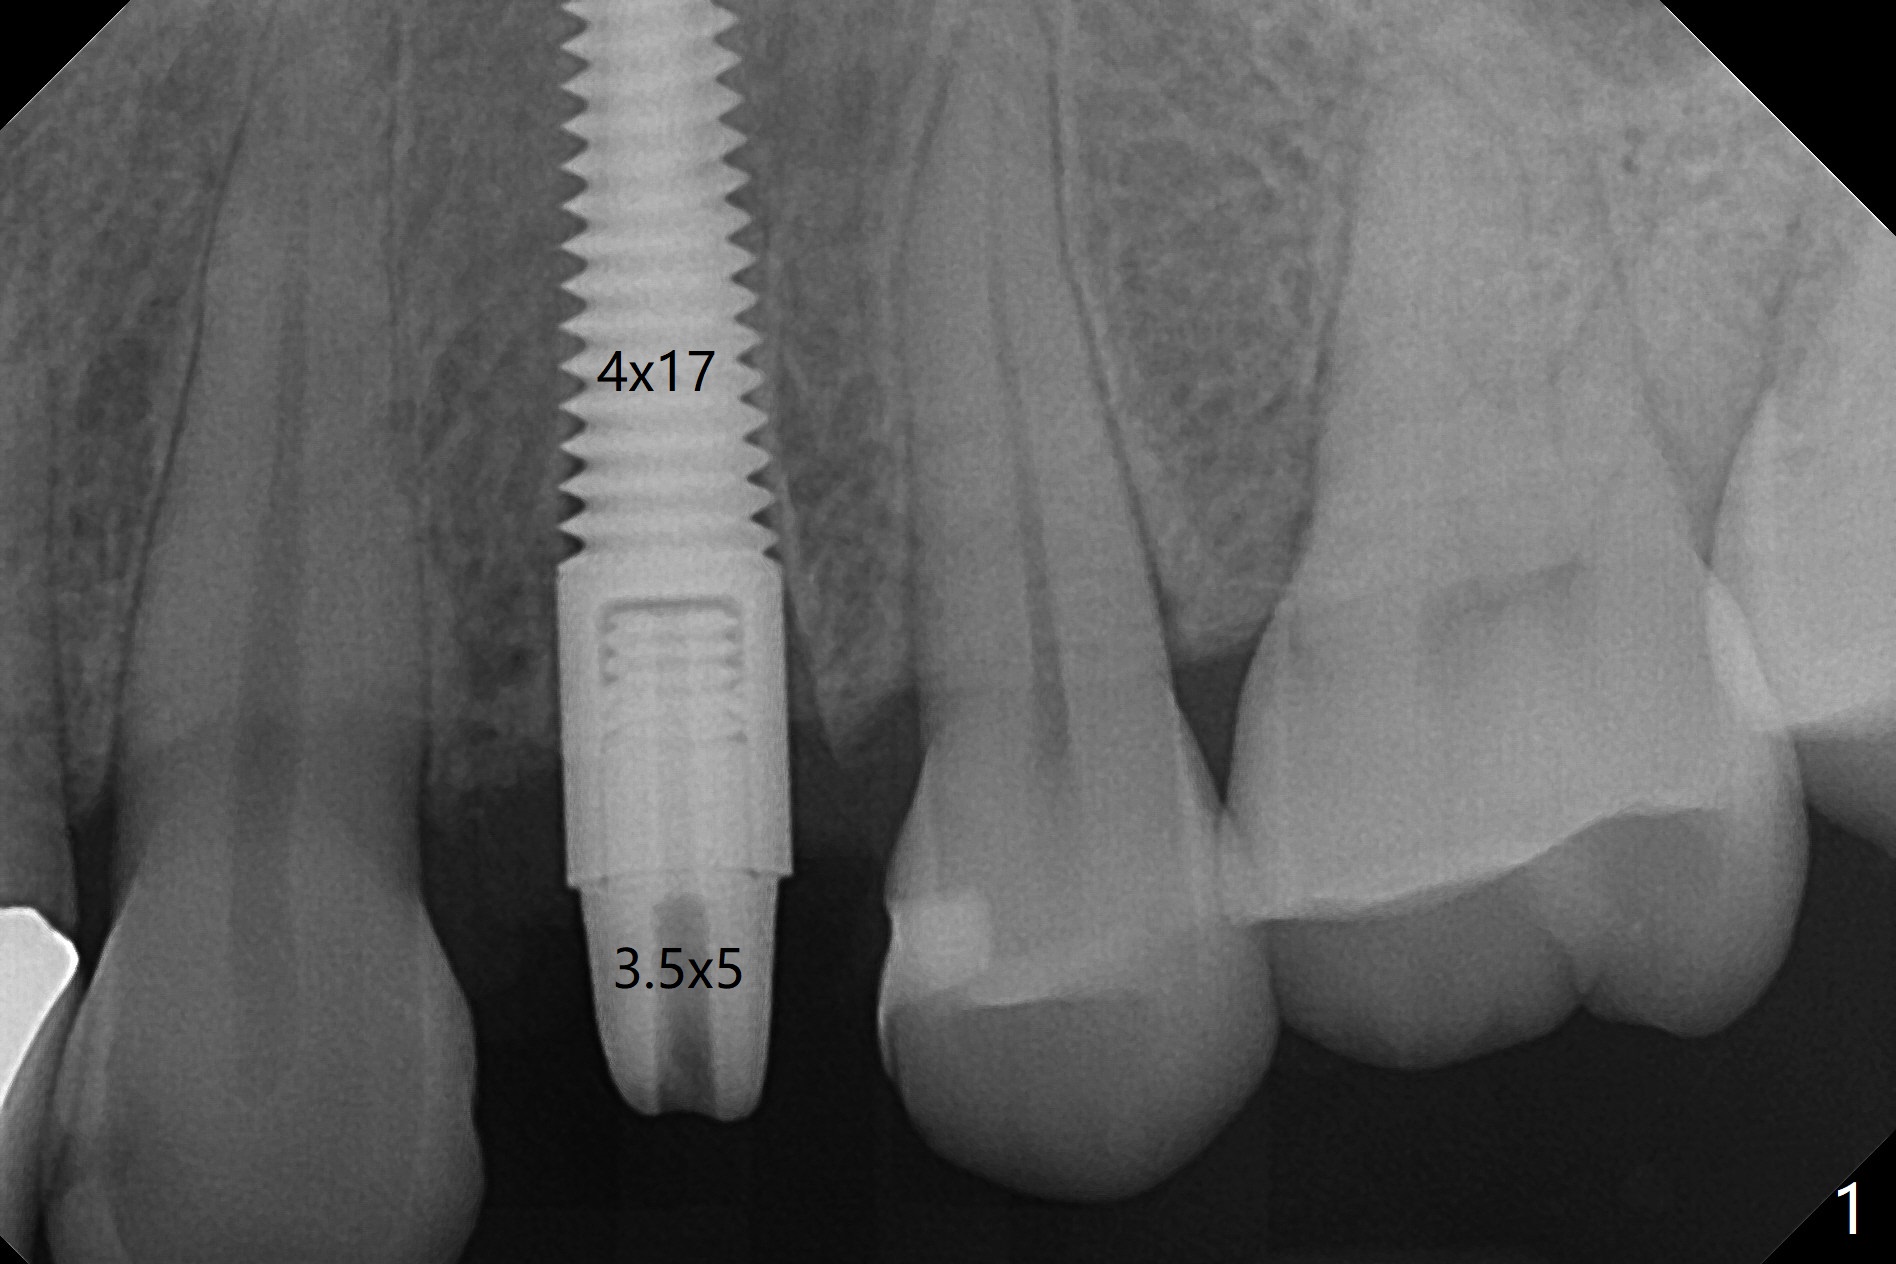

Since there is no buccal plate atrophy at 4, or 8, socket shield is not attempted at #31. Extraction turns out to be difficult because of tooth fracture. The buccal and palatal flaps have to be elevated minimally for tooth sectioning and purchase point formation. More surprising, a 4.5 mm implant appears to be too wide for the space; a 4x17 mm implant achieves insertion torque >60 Ncm (Fig.1,2). In fact Vanilla graft is placed before and after implantation. The advantage of bone graft before implant is that the graft is able to be placed as apical as possible to repair the apical defect if it is present. The disadvantage is hemorrhage. After placement of a 3.5x5 mm abutment, an immediate provisional is fabricated (Fig.3 P), which seems to be able to hold the separated buccal papillae in place. The latter heal around the immediate provisional 9 days postop (Fig.4). Because of the seal, the bone graft remains in place 1 month postop (Fig.5). There is no bone loss 5.5 months postop (Fig.6,7) or 6.5 months postop (immediately post cementation, Fig.8).